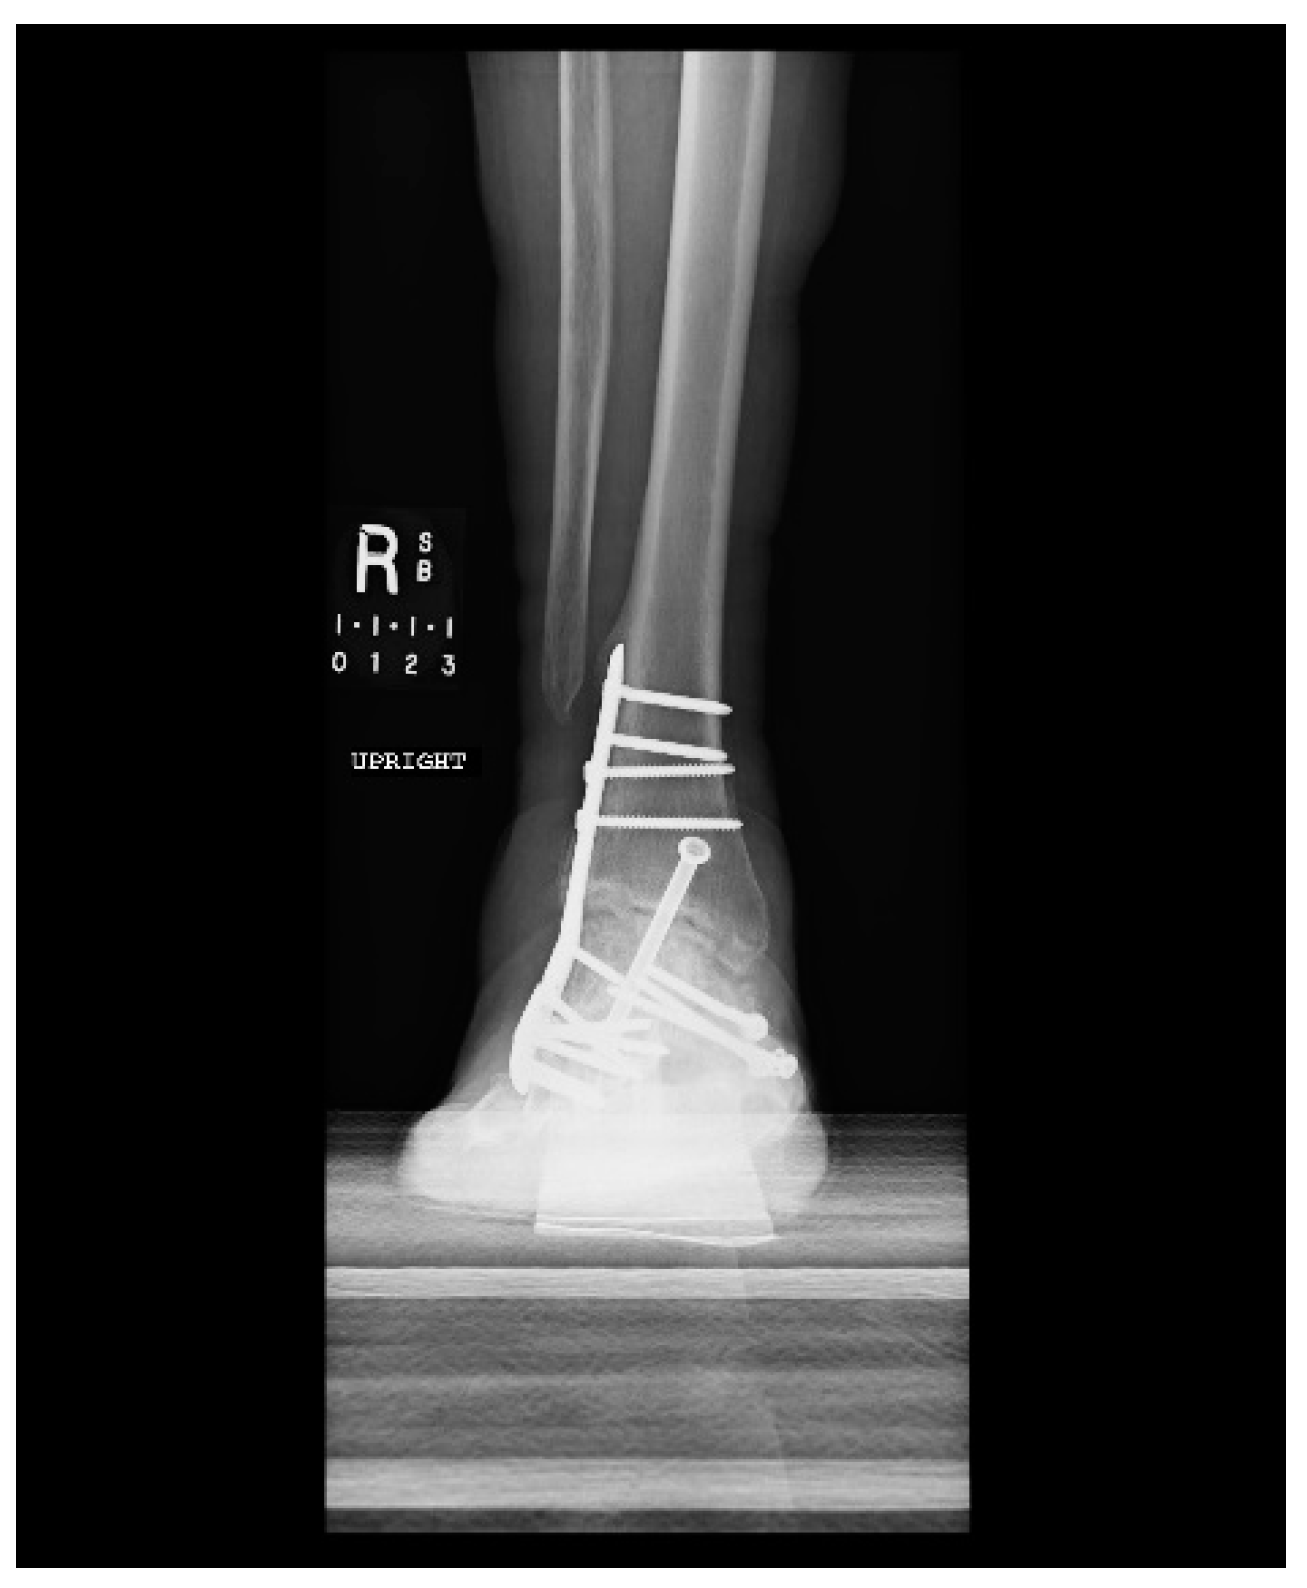

1.1. Case Presentation (Clinical Summary)

1.1.1. Initial Presentation

1.1.2. Operation

1.1.3. Post-Operative Follow-Up

1.1.4. Post-Operative Imaging